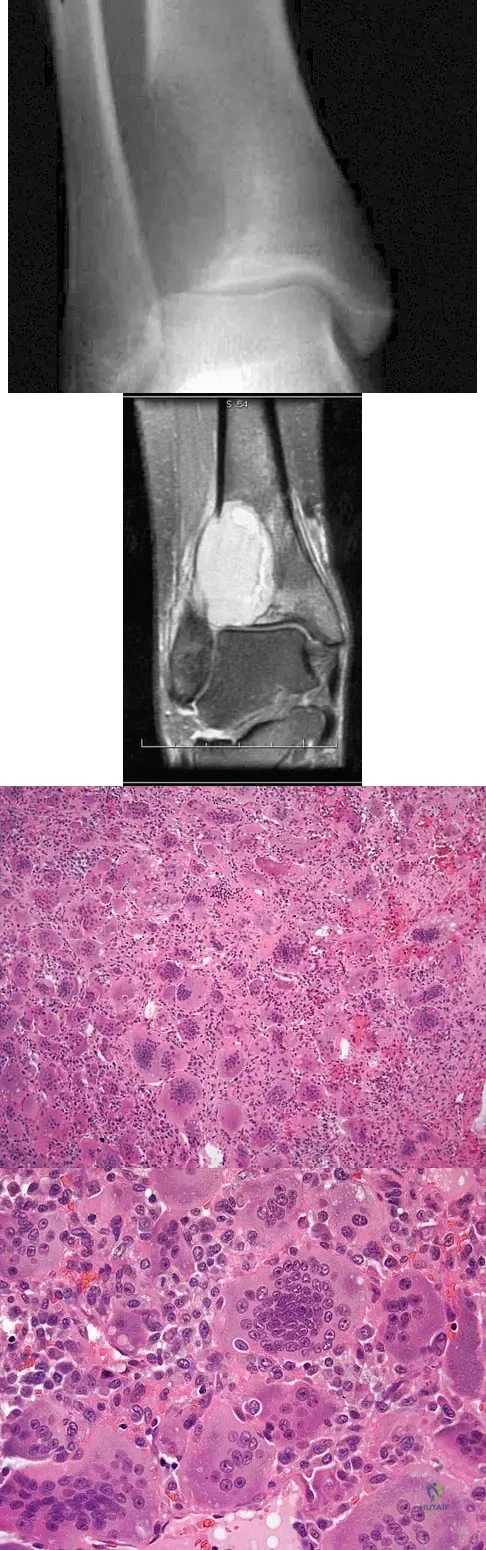

Figures 52a and 52b show the plain radiographs of a 12-year-old girl who has right distal leg pain. She reports that symptoms are present with weight-bearing activities and improve with rest. Examination reveals diffuse tenderness over the distal tibial metaphysis and mild swelling. A photomicrograph of the biopsy specimen is shown in Figure 52c. What is the most likely diagnosis?

Explanation